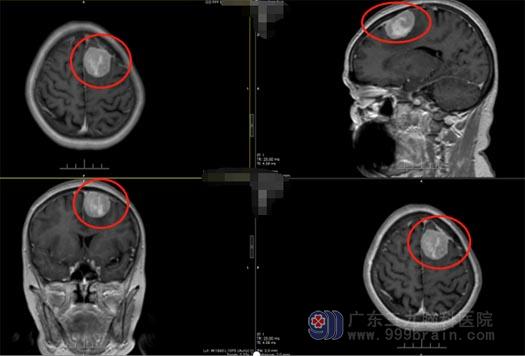

患者陈某,63岁,三周前开始出现无明显诱因嘴角抽搐,时间持续约5分钟,无其他症状,陈某开始并不在意。后面出现相同症状,遂到当地医院检查,查头部MR示左侧额部占位,进我院寻求进一步治疗。

在熟人的引导下就诊我院神经外五科王国良主任,结合患者的病史及检查初步诊断考虑脑膜瘤,建议手术治疗。

▲术前